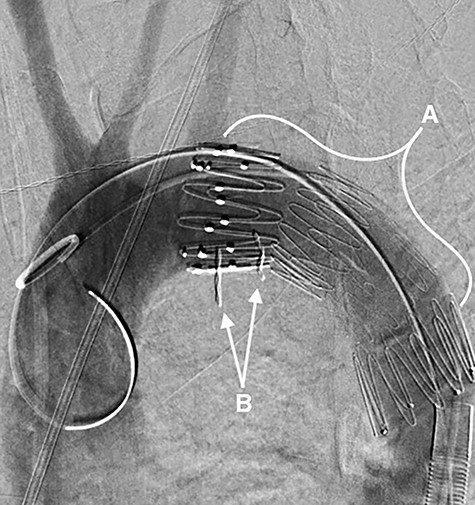

On arrival, the patient underwent an urgent thoracic endovascular aortic repair (TEVAR). This was successfully performed with a Zenith TX2® (Cook Medical, Indiana, USA) 28 × 80 mm endovascular stent-graft deployed across the aortic ulceration with the left subclavian artery spared, as demonstrated in Fig. 2. Post-procedure he was admitted to the intensive care unit (ICU).

A fluoroscopy image in the sagittal plane showing: (A) the stent-graft within the aorta and (B) the denture.